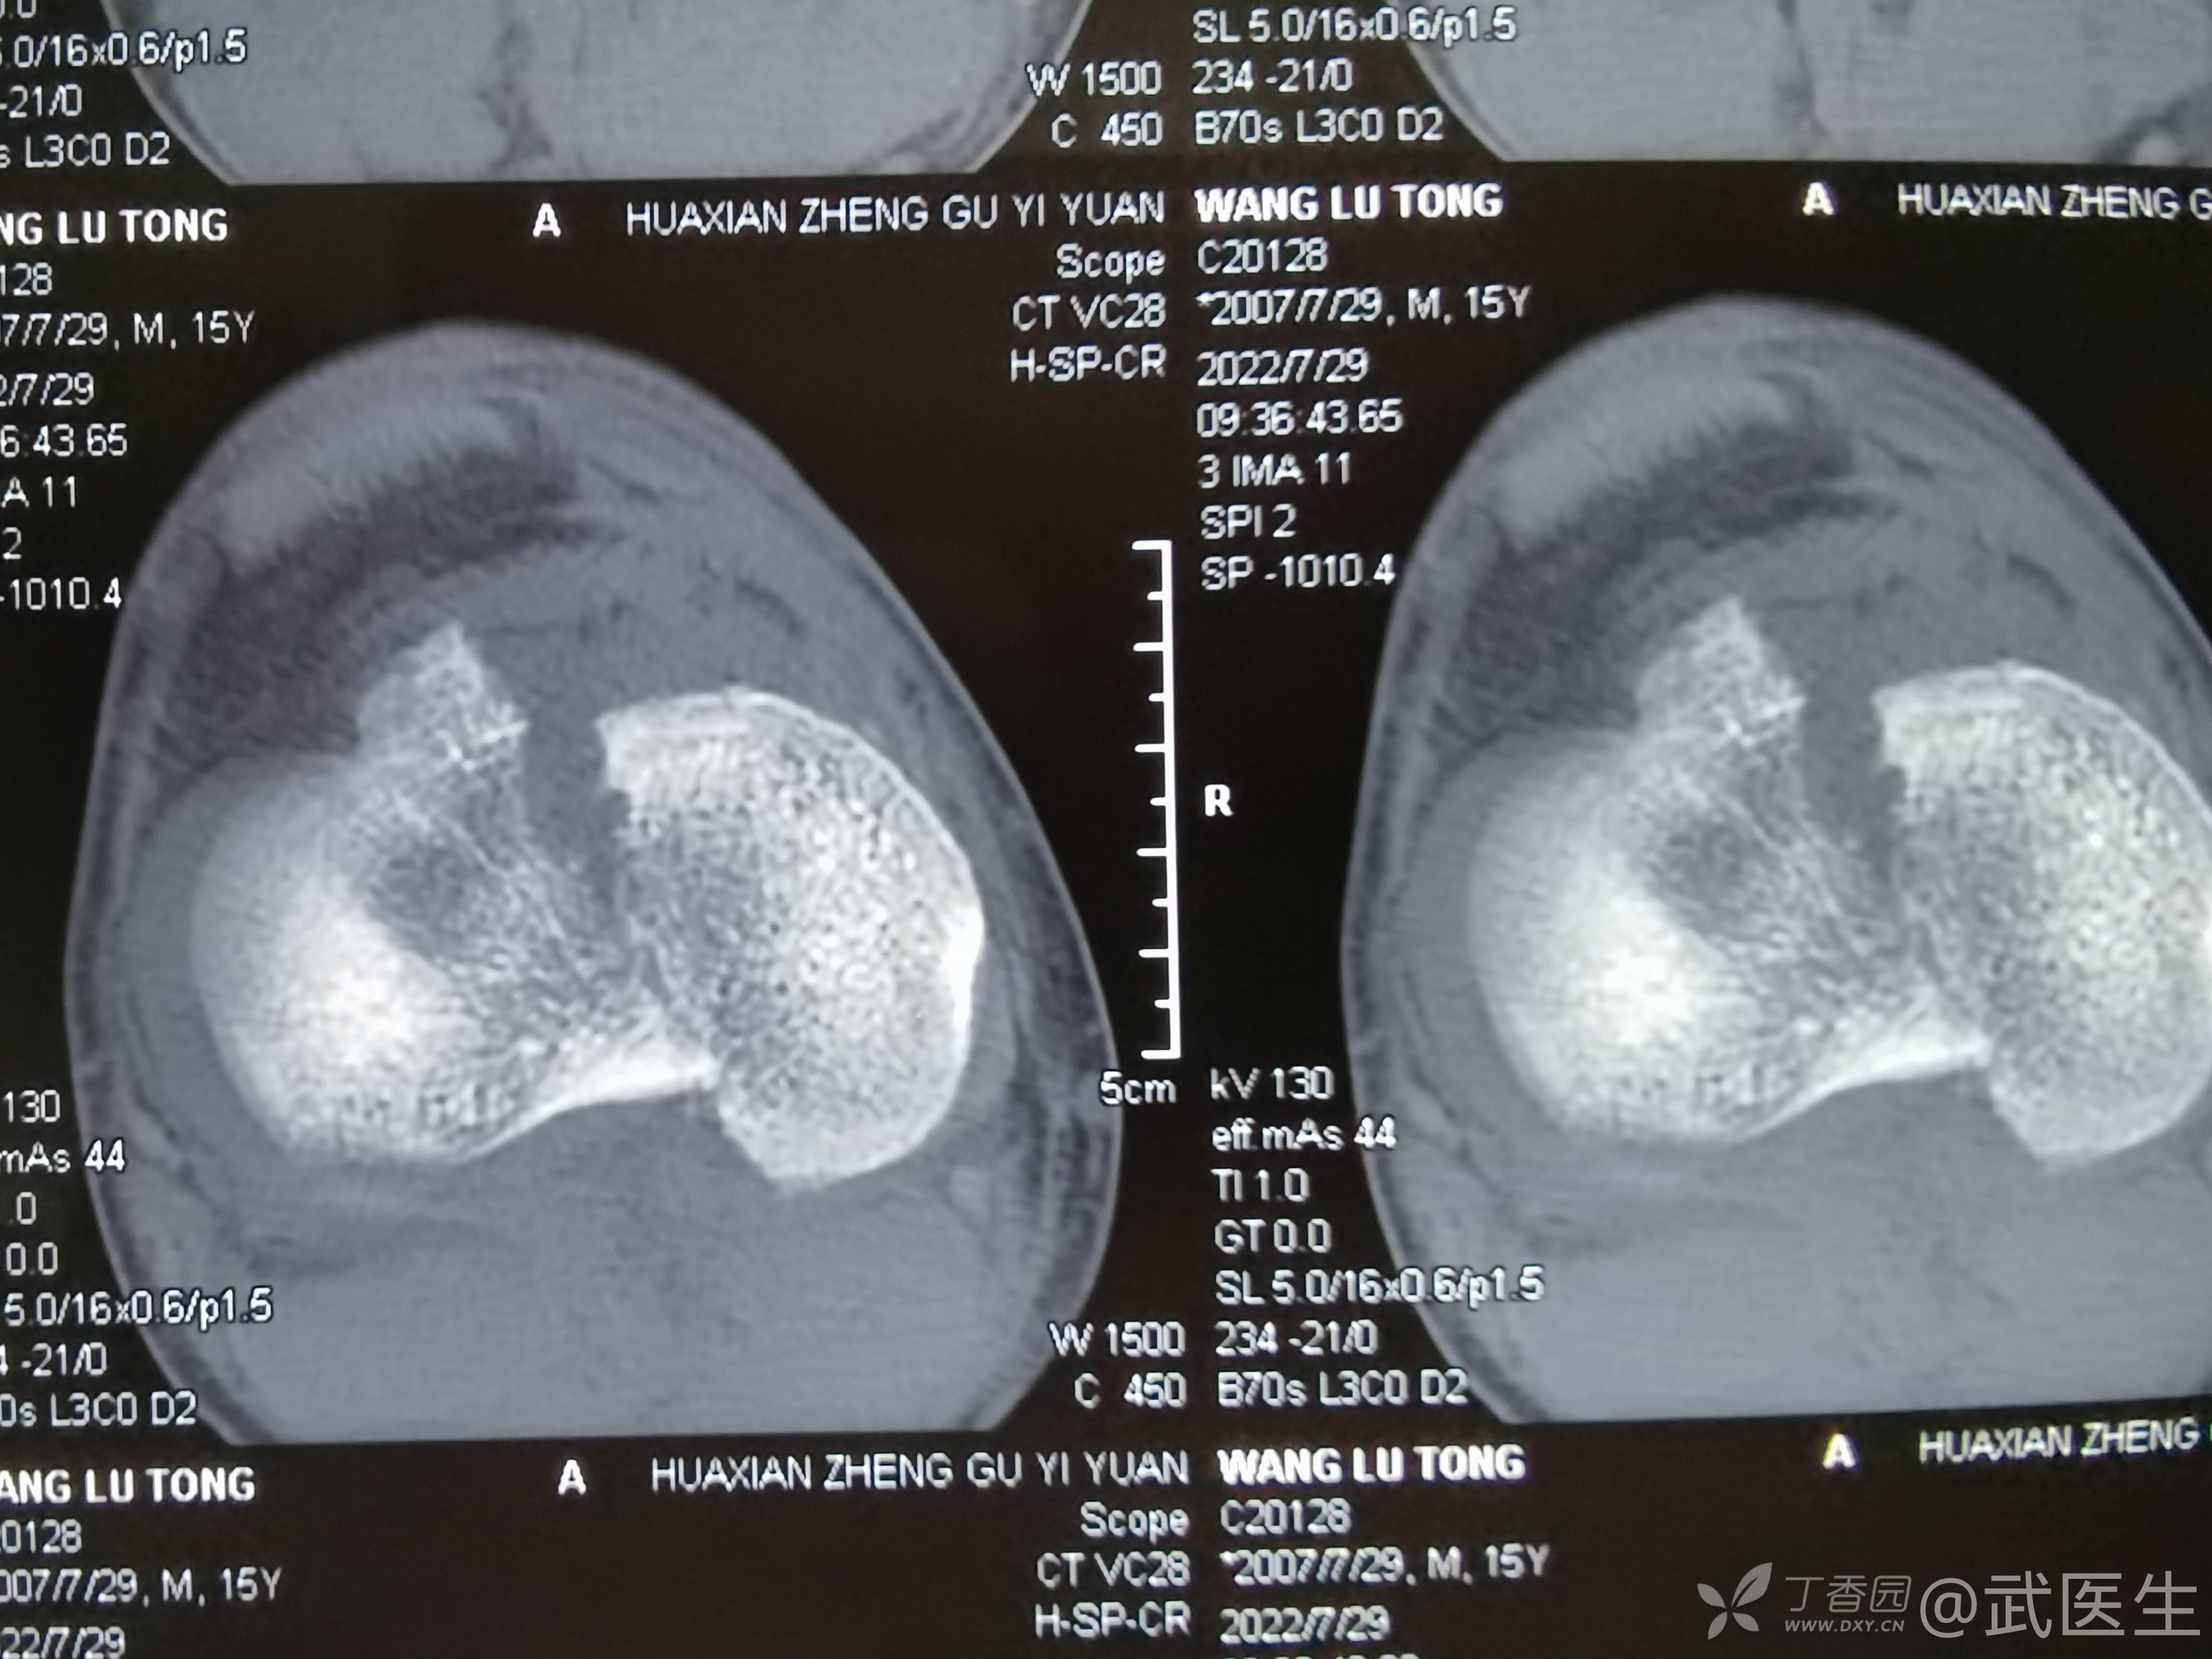

男,15岁,骑摩托车摔伤致右膝疼痛,出血,活动受限三小时就诊,门诊诊断“右胫骨平台骨折,右膝挫裂伤”急诊入院,片子如下,受伤体位照缺失

15岁,骨骺存在,关节加压固定,外侧板支撑